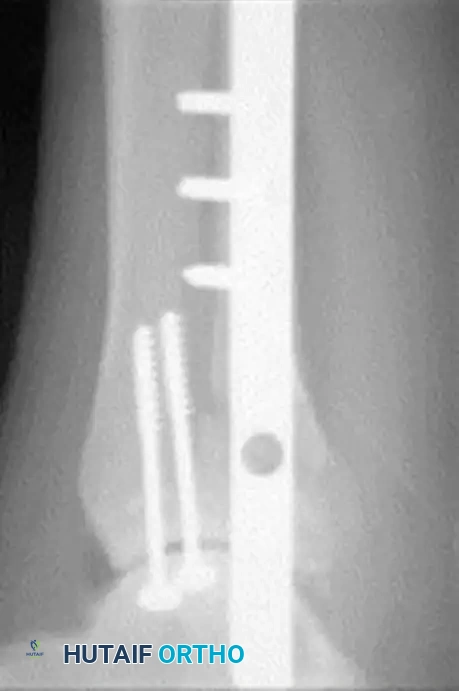

The following preoperative and postoperative radiographs demonstrate the successful application of augmented fixation in a young diabetic patient with a severe bimalleolar fracture-subluxation:

FIGURE 85-25 C-E: Postoperative fixation demonstrating robust fibular plating, medial malleolar screw fixation, and critical supplemental syndesmotic screws to reinforce the mortise.